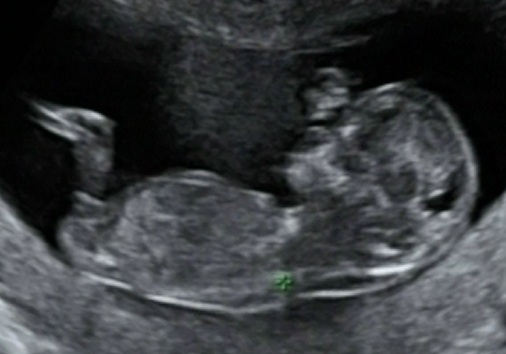

Hi just had my 12 week scan. I'm not sure what I'm looking for so these pictures could be no good.... I got them from the video so I can try and find others....